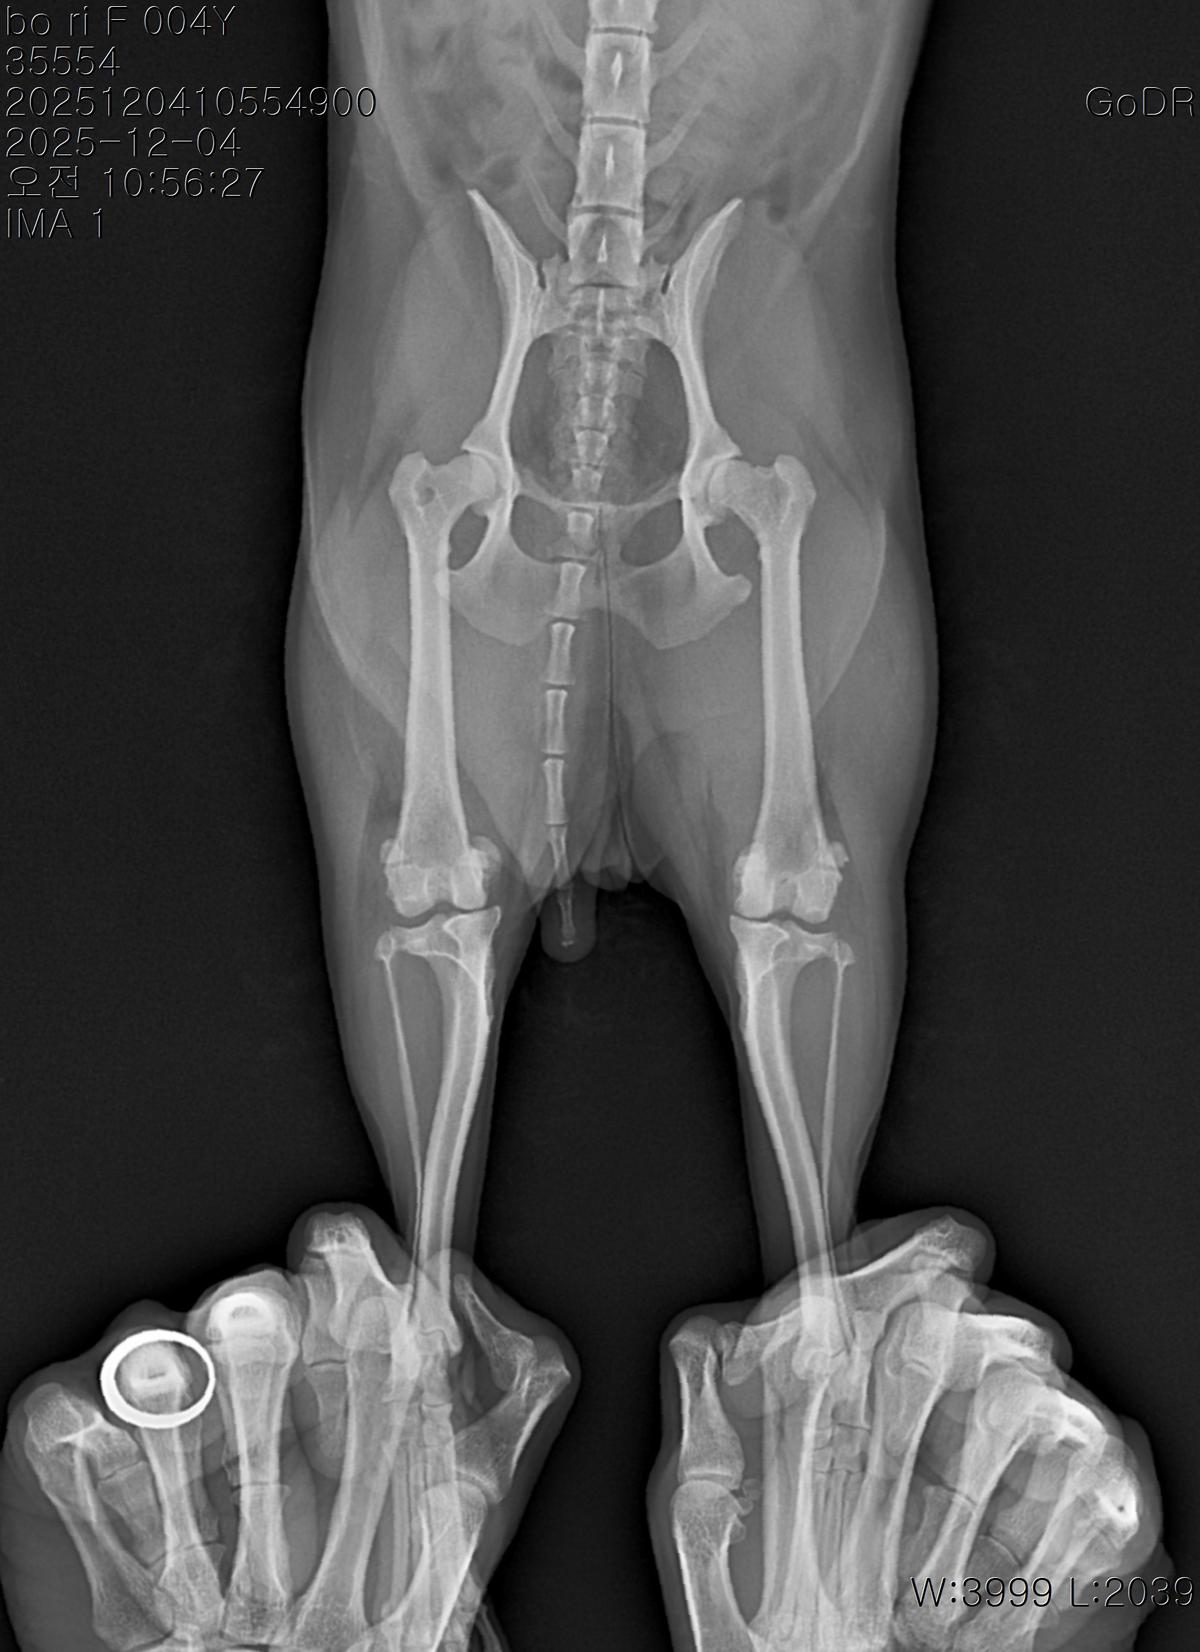

강아지 슬개골탈구 진단 받았습니다 몇군데 병원을 다녀봤는데 진단이 달라 궁금해서 질문 해봅니다 일단 저희 강아지는 오른쪽 다리를 갑자기 들고 다니고 절어 병원을 방문하게 되었고요 왼쪽은 증상이 없지만 오른쪽만 있는 상태였습니다 첫번째랑 두번째 병원에서는 슬개골 탈구 진행중이고 왼쪽이 3기 오른쪽이 2기 정도라고 했습니다 하지만 왼쪽은 아예 빠져있어 증상도 없고 아파하지도 않는다고 했고 오른쪽은 빠졌다 안빠졌다 해서 증상이 있다고 했고 십자인대가 파열된 걸론 보이지 않는다고 했습니다 그래서 양쪽 슬개골탈구 수술만 진행하면 된다고 했고요 근데 세번째 병원에서는 둘다 왼쪽이 좀 더 심한 슬개골 탈구 3기 정도라고 했고 오른쪽만 십자인대 부분파열이 보인다고 했습니다 그래서 십자인대 파열이 아닌 왼쪽은 굳이 수술할 필요가 없고 나중에 십자인대 파열이 오거나 증상이 나타나면 그때 수술하면 된다고 했습니다 그래서 오른쪽 슬개골탈구 수술과 tplo를 하는 방식으로 수술을 한다고 했습니다 여기서 궁금한점은 1. 십자인대 파열이 사진상으론 보이지 않는다고 하는데 사진상으로 알 수 있는 건가요? 2. 십자인대 파열이 아니면 슬개골탈구 수술을 굳이 할 필요 없다고 하셨는데 맞는 건가요? 3. 꼭 슬개골탈구와 십자인대 수술을 같이 해야 결과과 더 좋아지나요? 4. 사진상으로 십자인대와 슬개골 수술을 같이 해야할까요? 5. tplo 수술방법이 가장 안전하고 좋은 수술방법인가요? 6. 슬개골탈구로 인해 십자인대가 끊어지는건 아니라고 들었는데 맞나요? 슬개골 탈구 수술로 십자인대를 예방할 수 있나요?